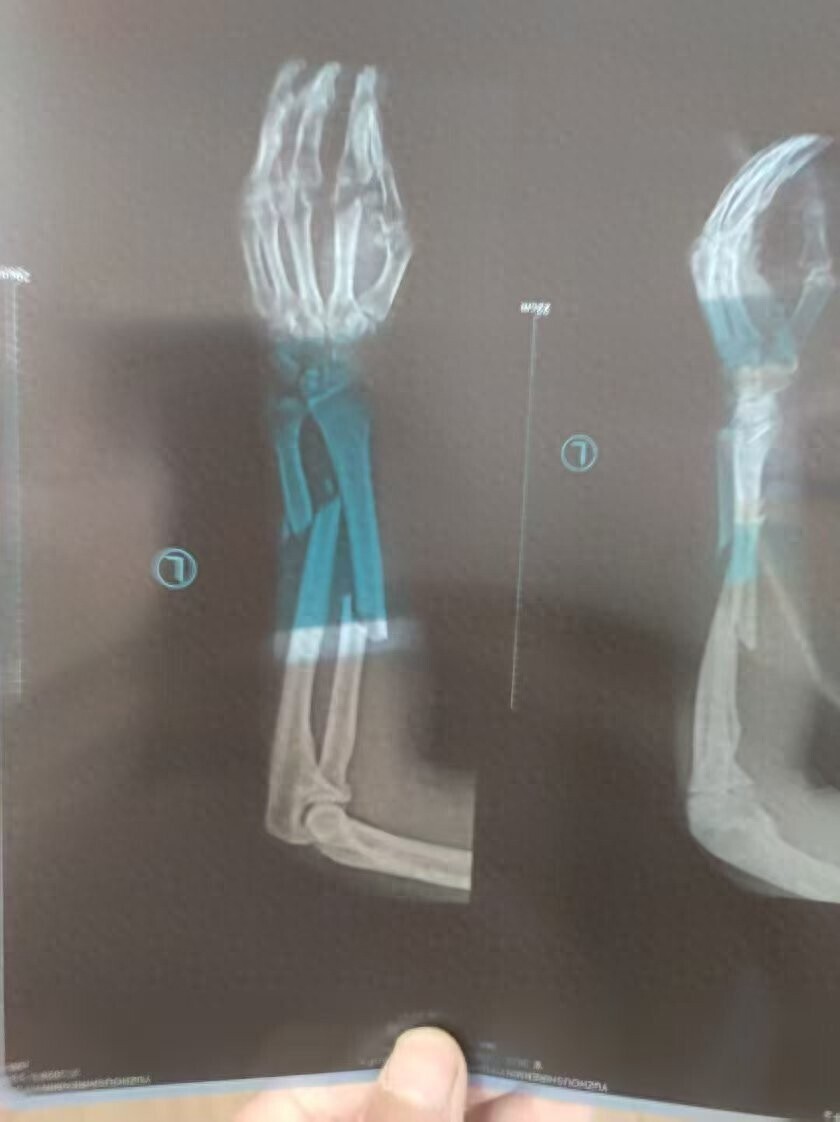

“男子被钻机拧断胳膊,难获37万工伤补助金”: 相关方支付10万元,承诺余款分期结清

河南男子王先生在煤矿巷道中打钻施工时胳膊被钻机拧断,被鉴定为八级伤残,劳动仲裁认定企业需支付王先生工伤补助金37万余元,煤矿却迟迟不支付,法院查封了等值的800吨煤,却在拍卖前被矿上卖掉了。10月16日,华商报大风新闻以《大风追踪 | “男子被钻机拧断胳膊,难获37万工伤补助金”:法院查封的800吨煤,拍卖前被矿方私售》为题对此事进行了报道,引起当地相关部门和涉事单位的重视。